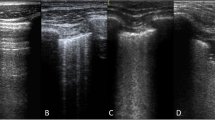

Lung ultrasound

Lung ultrasound (LUS) was performed at 3-time points; baseline (at enrolment), 24 h and 48 h and timed with other measurements. Scans were performed using the Venue™ Ultrasound System (GE Healthcare) with the L8-18i linear array hockey stick, ultrasound probe transducer (5-9 MHz) and a lung pre-set focused at the level of the pleural line. The depth of penetration was standardized to 4–8 cm. Video images were recorded from 4 regions for each hemithorax: zone 1, superior in the mid-clavicular line; zone 2, inferior in the mid clavicular line; zone 3, superior in the mid-axillary line; and zone 4 inferior in the mid axillary line capturing the costo-diaphragmatic angle. A B-line was identified as a continuous echogenic line arising from the pleural margin that obliterated an A-line and extended the length of the image. The most perpendicular intercostal space to the ultrasound beam was chosen and then visualised throughout a respiratory cycle. If more than one intercostal space met these criteria, the space with the greatest number of B-lines was included. The number of B-lines was counted in one intercostal space per image and the lung ultrasound score (LUS) for each region was calculated as follows (Supplementary Fig. 1):

0: A-pattern (defined by the presence of A-lines only);

1: B-pattern (defined as the presence of 1 or 2 well-spaced B-lines);

2: severe B pattern (defined as the presence of ≥ 3 well-spaced B-lines or coalescent B-lines; and.

3: extended consolidation is defined as the presence of consolidation limited to the subpleural space or any pleural effusion. (similar to other scoring methodologies) [26].

Ultrasound imaging was performed by BG, SK or VM who were trained by sonographers prior to the study commencement. The LUS scores were attributed by a clinician with expertise in lung ultrasound (AOB) who was blinded to other measurements. A maximum total LUS for each period was 24. If a lung zone was considered not assessable, or not available, the median score for that hemithorax was manually imputed. If more than two segments were not assessable, then the score was not analysed.